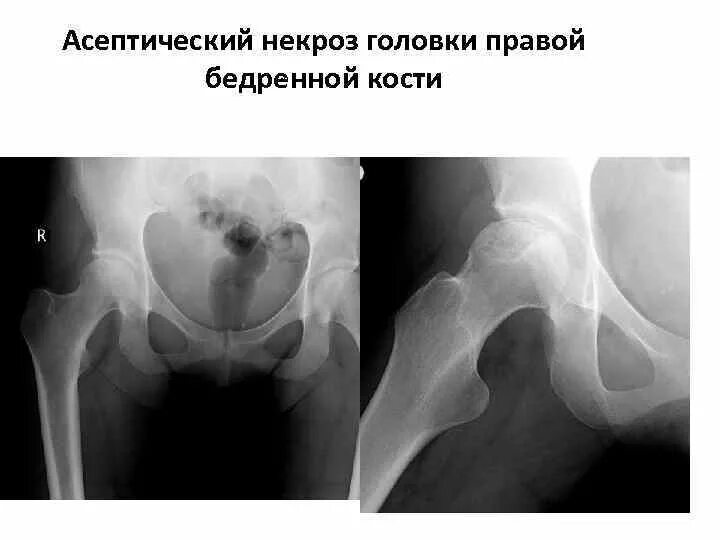

Некроз головки тазобедренного сустава лечение